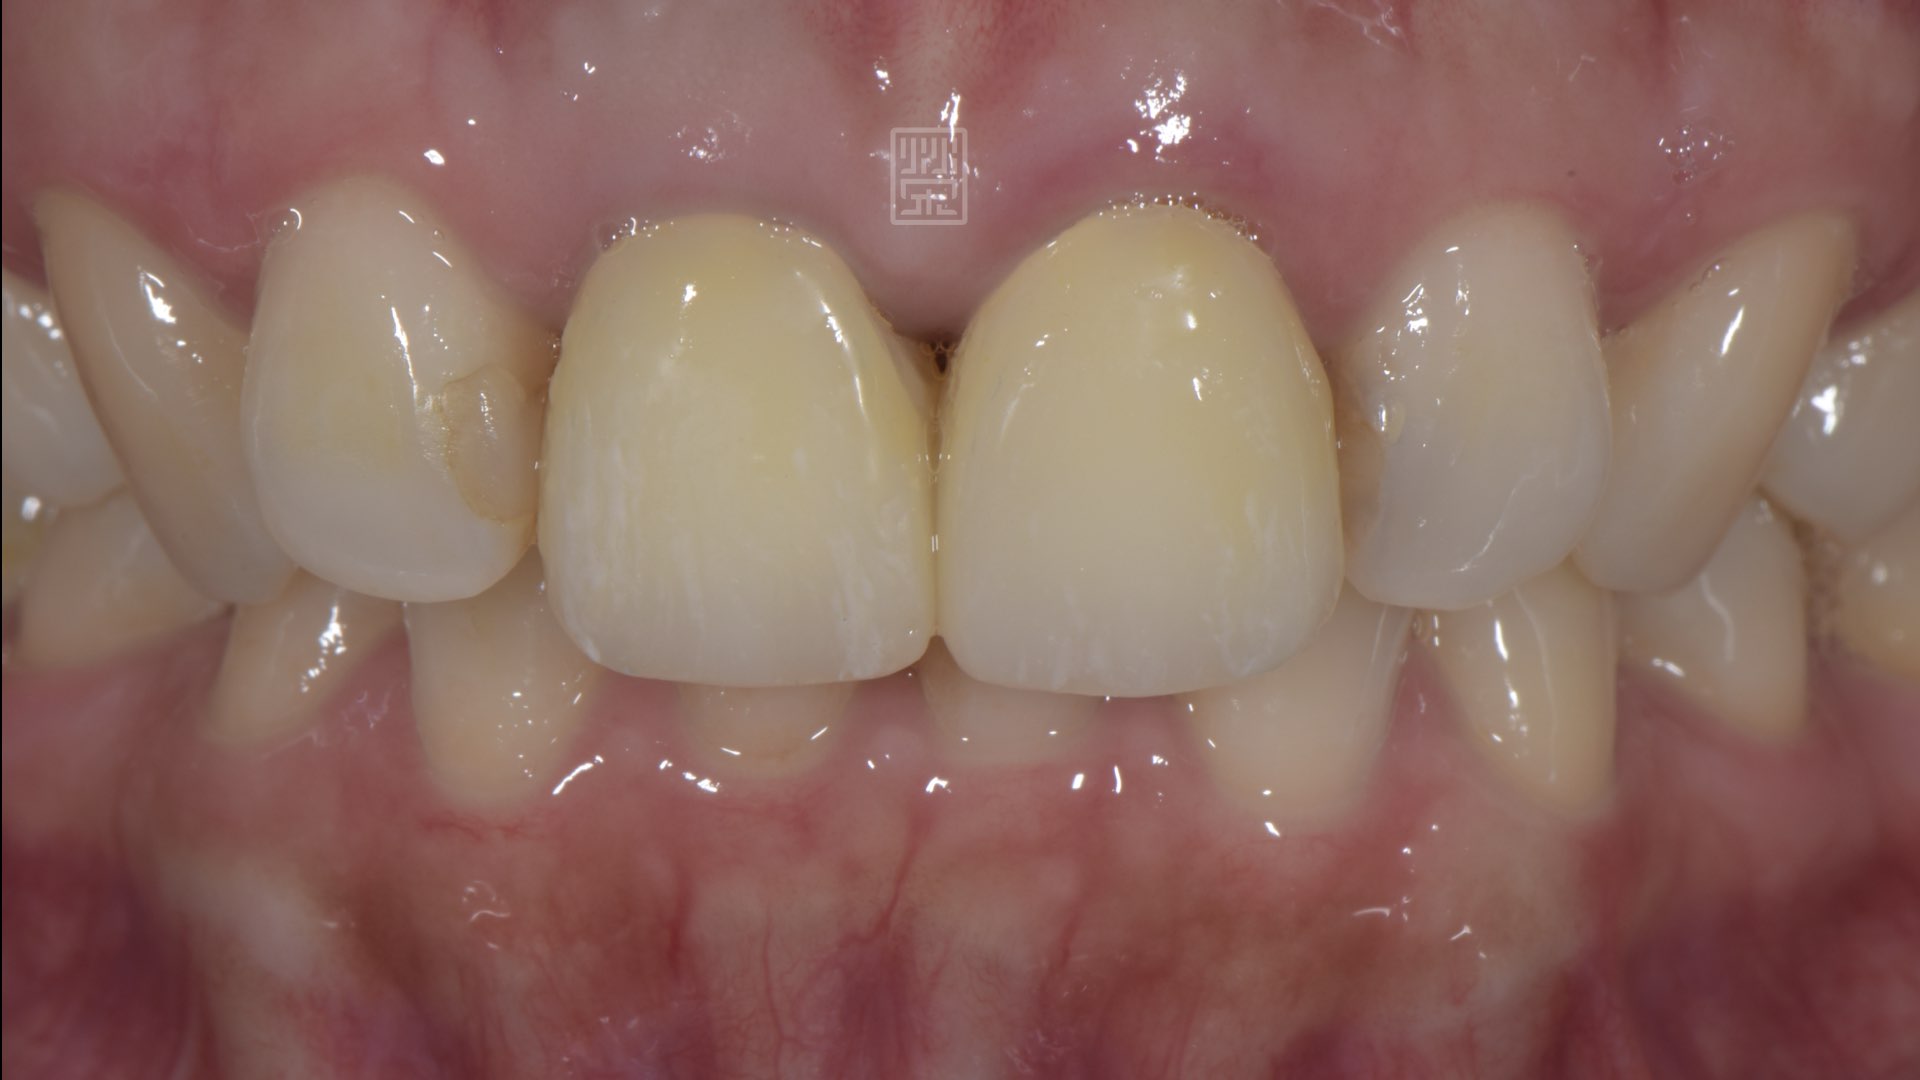

六週後牙齦穩定

全瓷冠完成